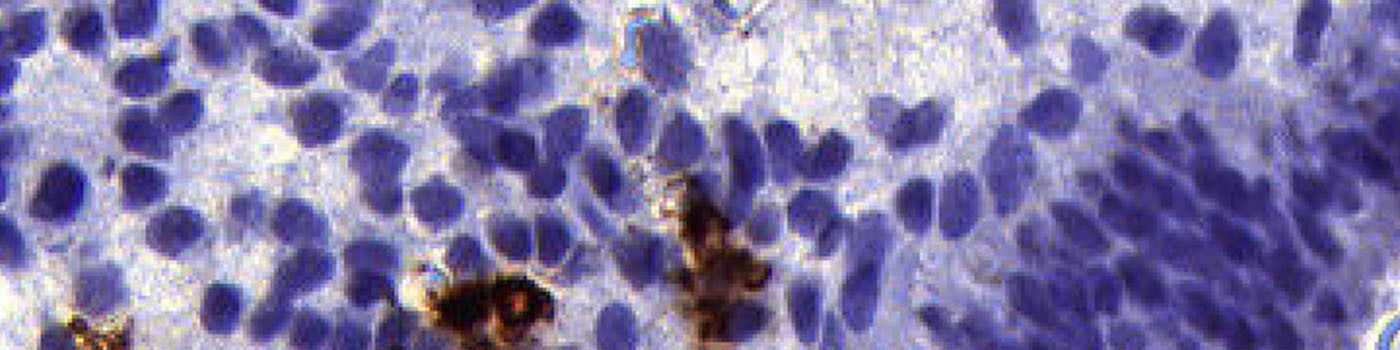

Uterine natural killer (uNK) cells in the pre-pregnancy endometrium have been associated with recurrent miscarriage. Immunohistochemical (IHC) analysis of endometrial tissue sections has demonstrated increased density of CD56+ CD16- uNK cells in the mid-luteal phase endometrium in women suffering from idiopathic recurrent miscarriage and recurrent implantation failure compared to fertile controls, see [1].

This APP measures the ratio of uNK cells among the stromal cells near the epithelial edge. Cells in the glands and in the epithelial edge itself do not contribute to the calculations.

This APP is designed to work on approx. 3 µm sections of endometrial tissue immunostained with anti-CD56 monoclonal antibody and counterstained with Mayer’s haematoxylin.

The second step identifies the epithelial edge within the tissue based on saturation and local shape. It outlines a final ROI up to 300 µm into the tissue from the epithelial edge, still excluding glands (see FIGURE 1, 2, 3, 4).

The third step identifies uNK cells and stromal cells within the final ROI, and calculates the relevant output variables, including the ratio of uterine Natural Killer (uNK) cells to stromal cells (see FIGURE 5 and 6).